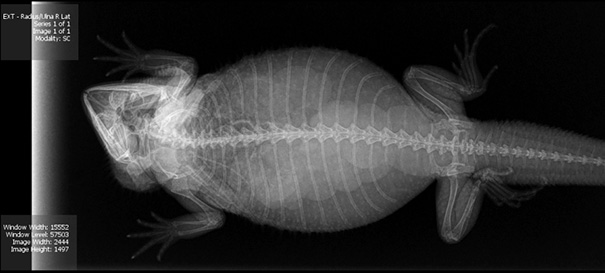

X-Ray Of My Bearded Dragon Kora